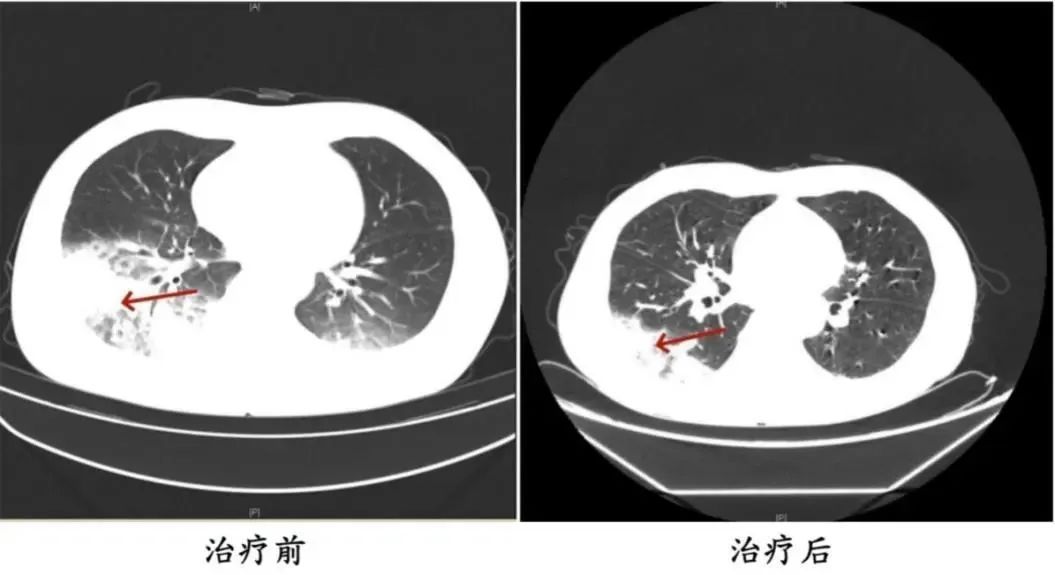

▲周先生治疗前后的肺部CT影像

家人见状,立即将他送医。胸部CT显示李先生的左肺已出现大面积白色影像,几乎占据一半肺部。经过检测,最终确认是嗜肺军团菌肺炎。

医生询问发现,周先生此前驾车出差,因为天气热,他启动了久未清洗的车载空调,每天在车上的时间超过十个小时,回来后就出现了如上症状。经过检查,最终确诊为军团菌肺炎。